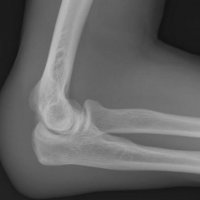

Olecranon bursitis refers to inflammation of the olecranon bursa. The olecranon bursa is a subcutaneous space lined with a synovial membrane that secretes fluid to provide smooth and almost frictionless motion between the skin, the subcutaneous tissues, and the olecranon. Because of its superficial location, it is a common site for injury, inflammation, and infection. Repeated traumatization of the elbows at work led to common terms for different forms of occupational bursitis such as “student's elbow” or “miner's elbow”.

Approximately one third of the cases of olecranon bursitis are septic. Many patients with septic olecranon bursitis lack a history of trauma or a visible injury over the olecranon.

Lateral radiograph of the elbow reveals soft tissue swelling superficial to the olecranon. Ultrasound may show a fluid collection in the olecranon bursa, features of synovial proliferation and/or hyperemia.

CT will show fluid density at the subcutaneous tissue superficial to the elbow. Bursal fluid collection in MRI has the following features: hypointense-T1, mainly hyperintense-T2, and enhancement of bursal margins in post contrast imaging.